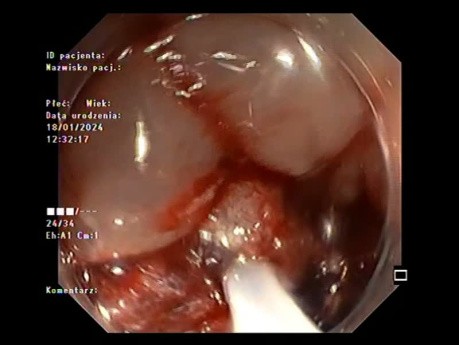

Kolonoskopia: mukozektomia endoskopowa (EMR)...

W filmie pokazano mukozektomię endoskopową (EMR) guza LST-G-MIX odbytnicy. Podczas zabiegów endoskopowych kluczowe jest odpowiednie zaplanowanie zabiegu. Zaczęto od wstrzyknięcia podśluzówkowego 40 ml...